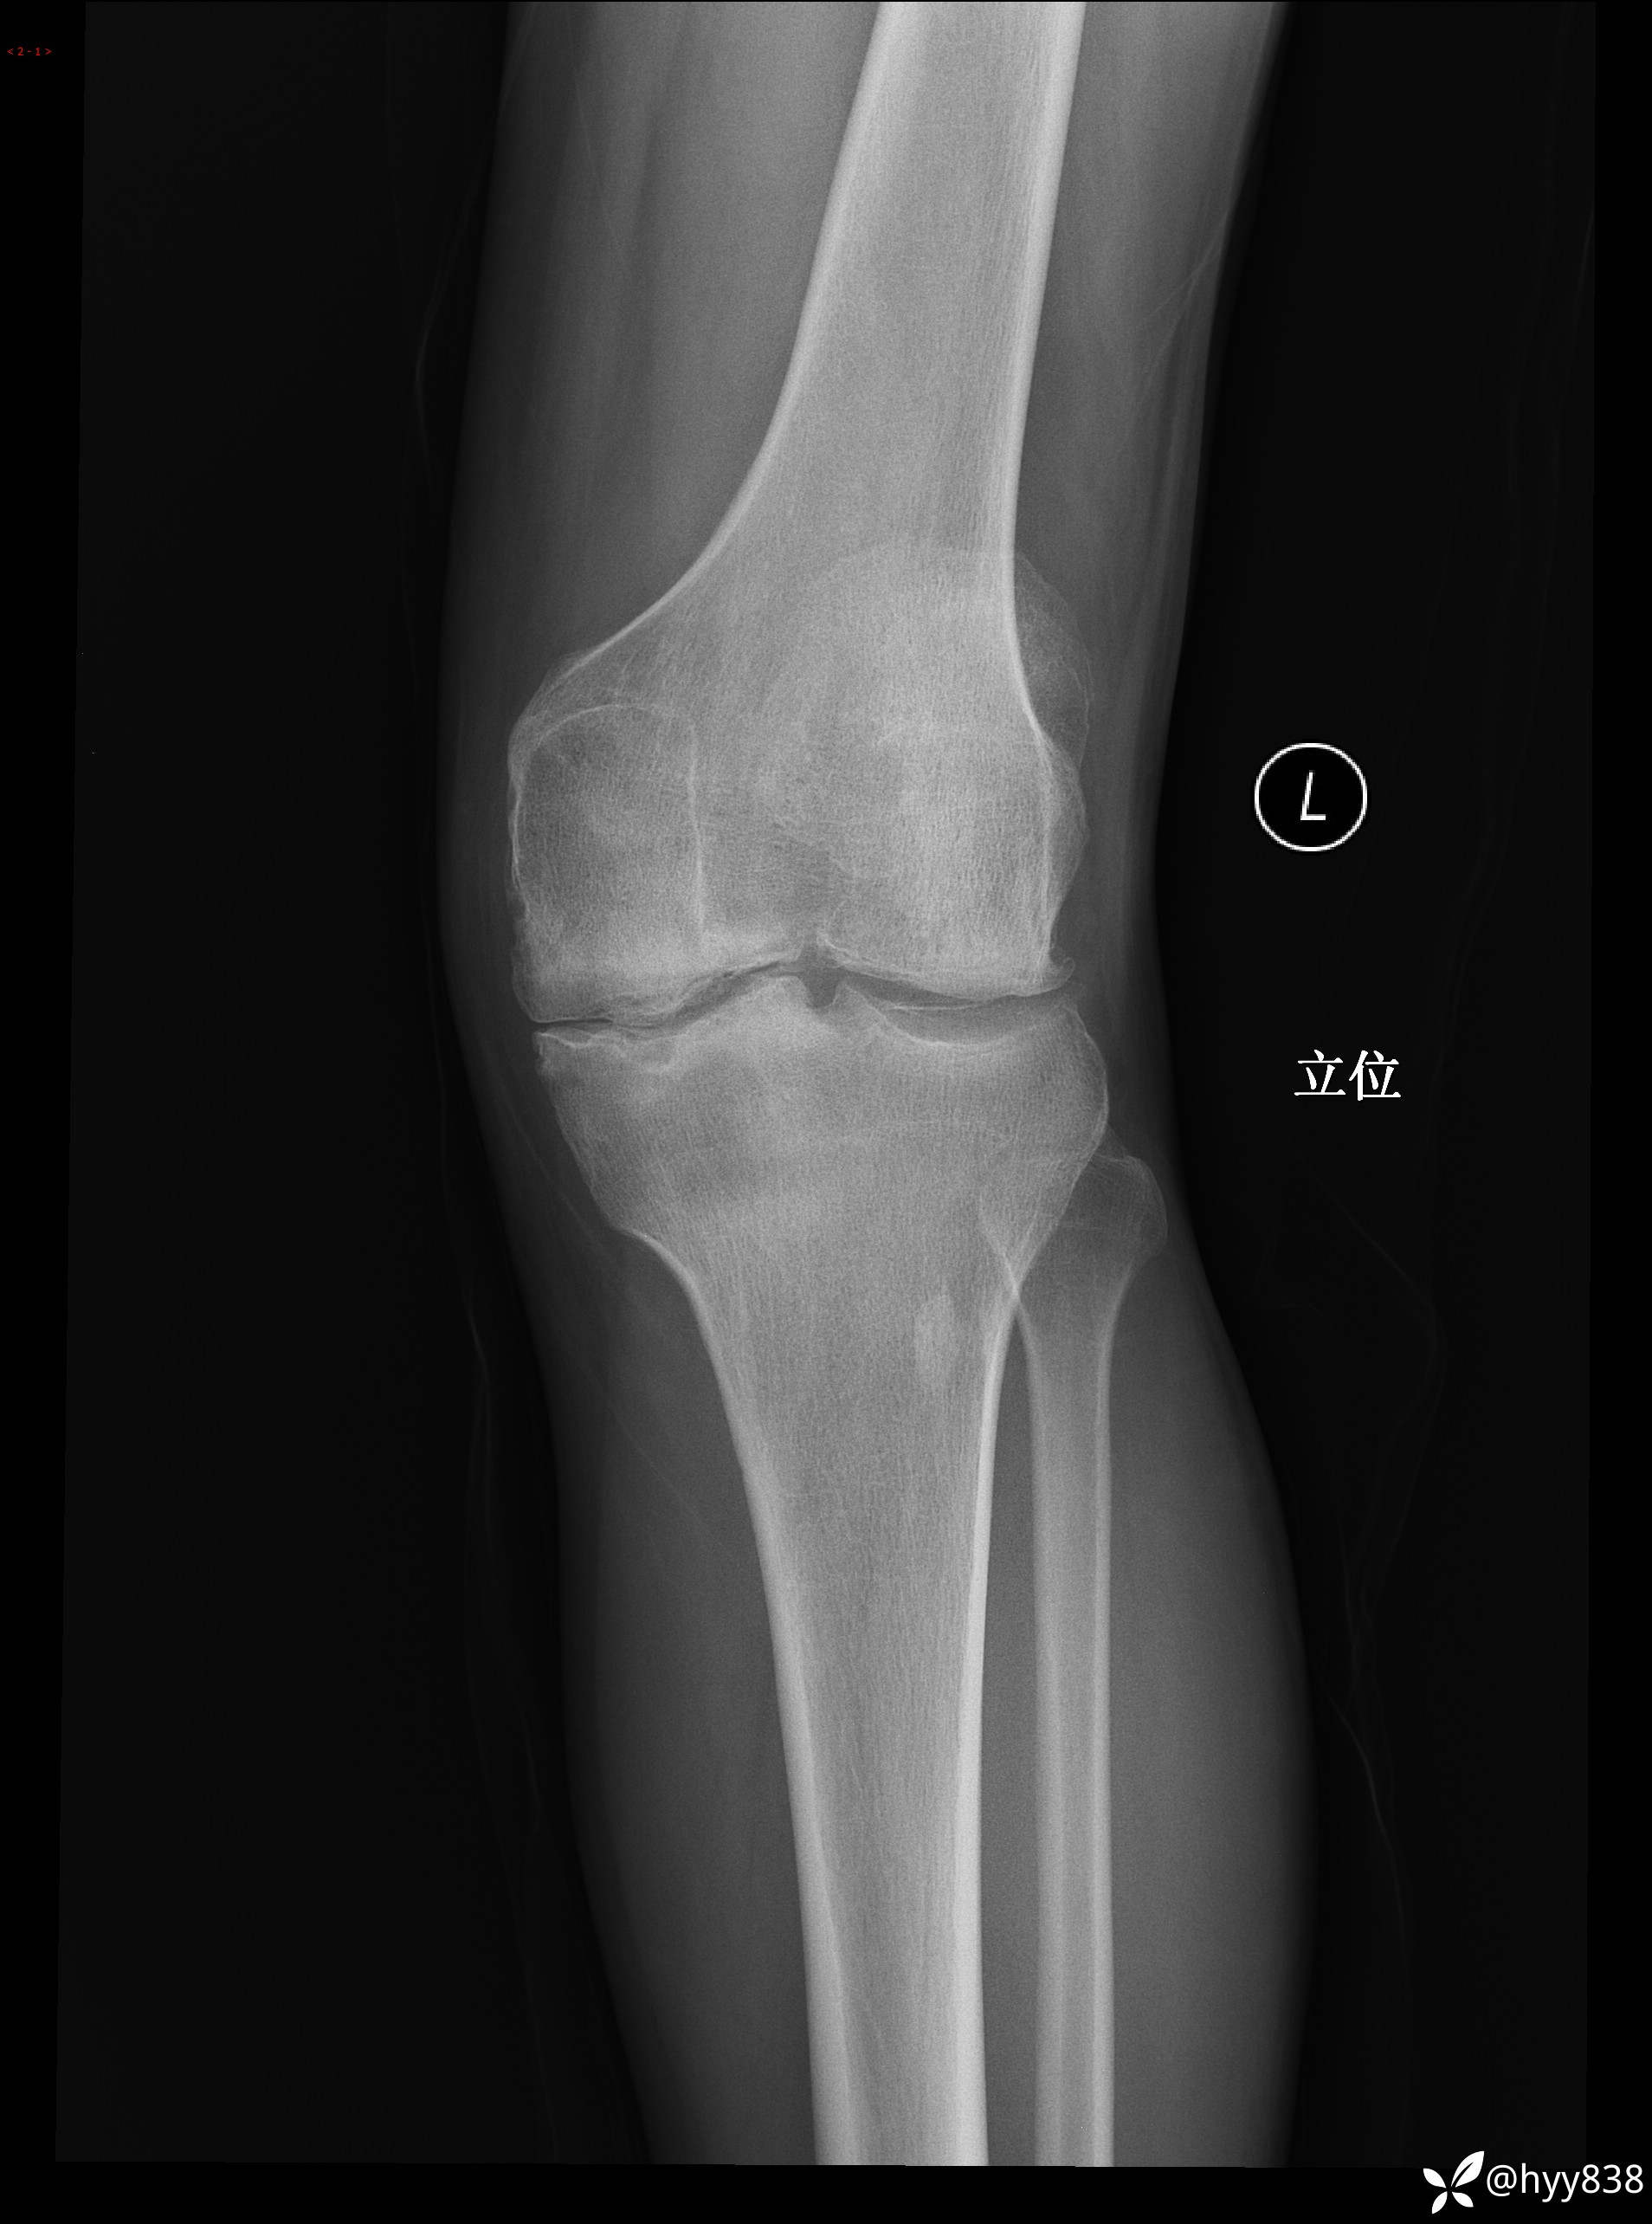

膝关节平片